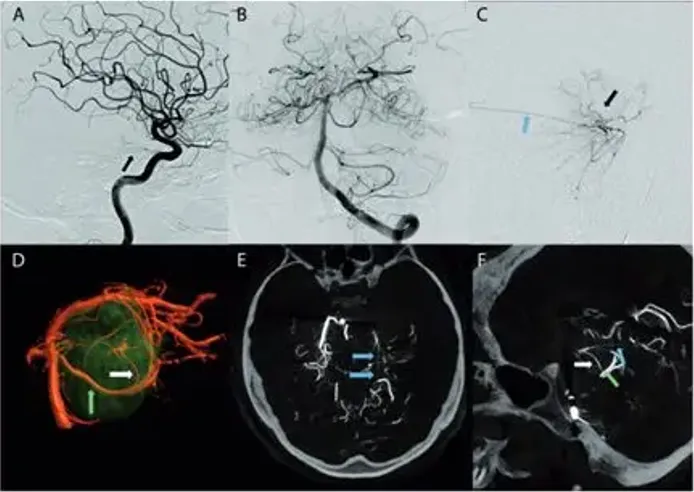

负责主治的福教授,同其手术团队联合会诊后,为患者确定了具有针对性的手术方案——术前需进行血管造影并栓塞,以确定主要动脉供血者,促进手术切除及降低手术风险,再行手术切除。

术前栓塞

用1毫升氰基丙烯酸酯胶(Glubran,Glubran-2,GEM,Viareggio,Italy)碘油(4ml of lipiodol)堵塞供血动脉,造影结果良好,无并发症。术后脑MR显示脑膜瘤部分断流,无脑水肿。

(患者脑血管造影图)